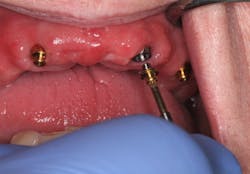

Technique for determining the need for a reline—maxilla:

Since a minimum of four implants are in place, it is very difficult to feel a "squish." Instead, I line the inside of the denture with light-body impression material, seat the denture on the abutments, and remove the denture after the material sets. Probe the impression material in multiple locations (figures 16–18). If probing is shallow and consistent through the denture, a reline is not indicated. If any areas are deeper, a reline is indicated. Note: The attachments are clearly visible in Figures 17 and 18, but often a thin layer of impression material will cover them.